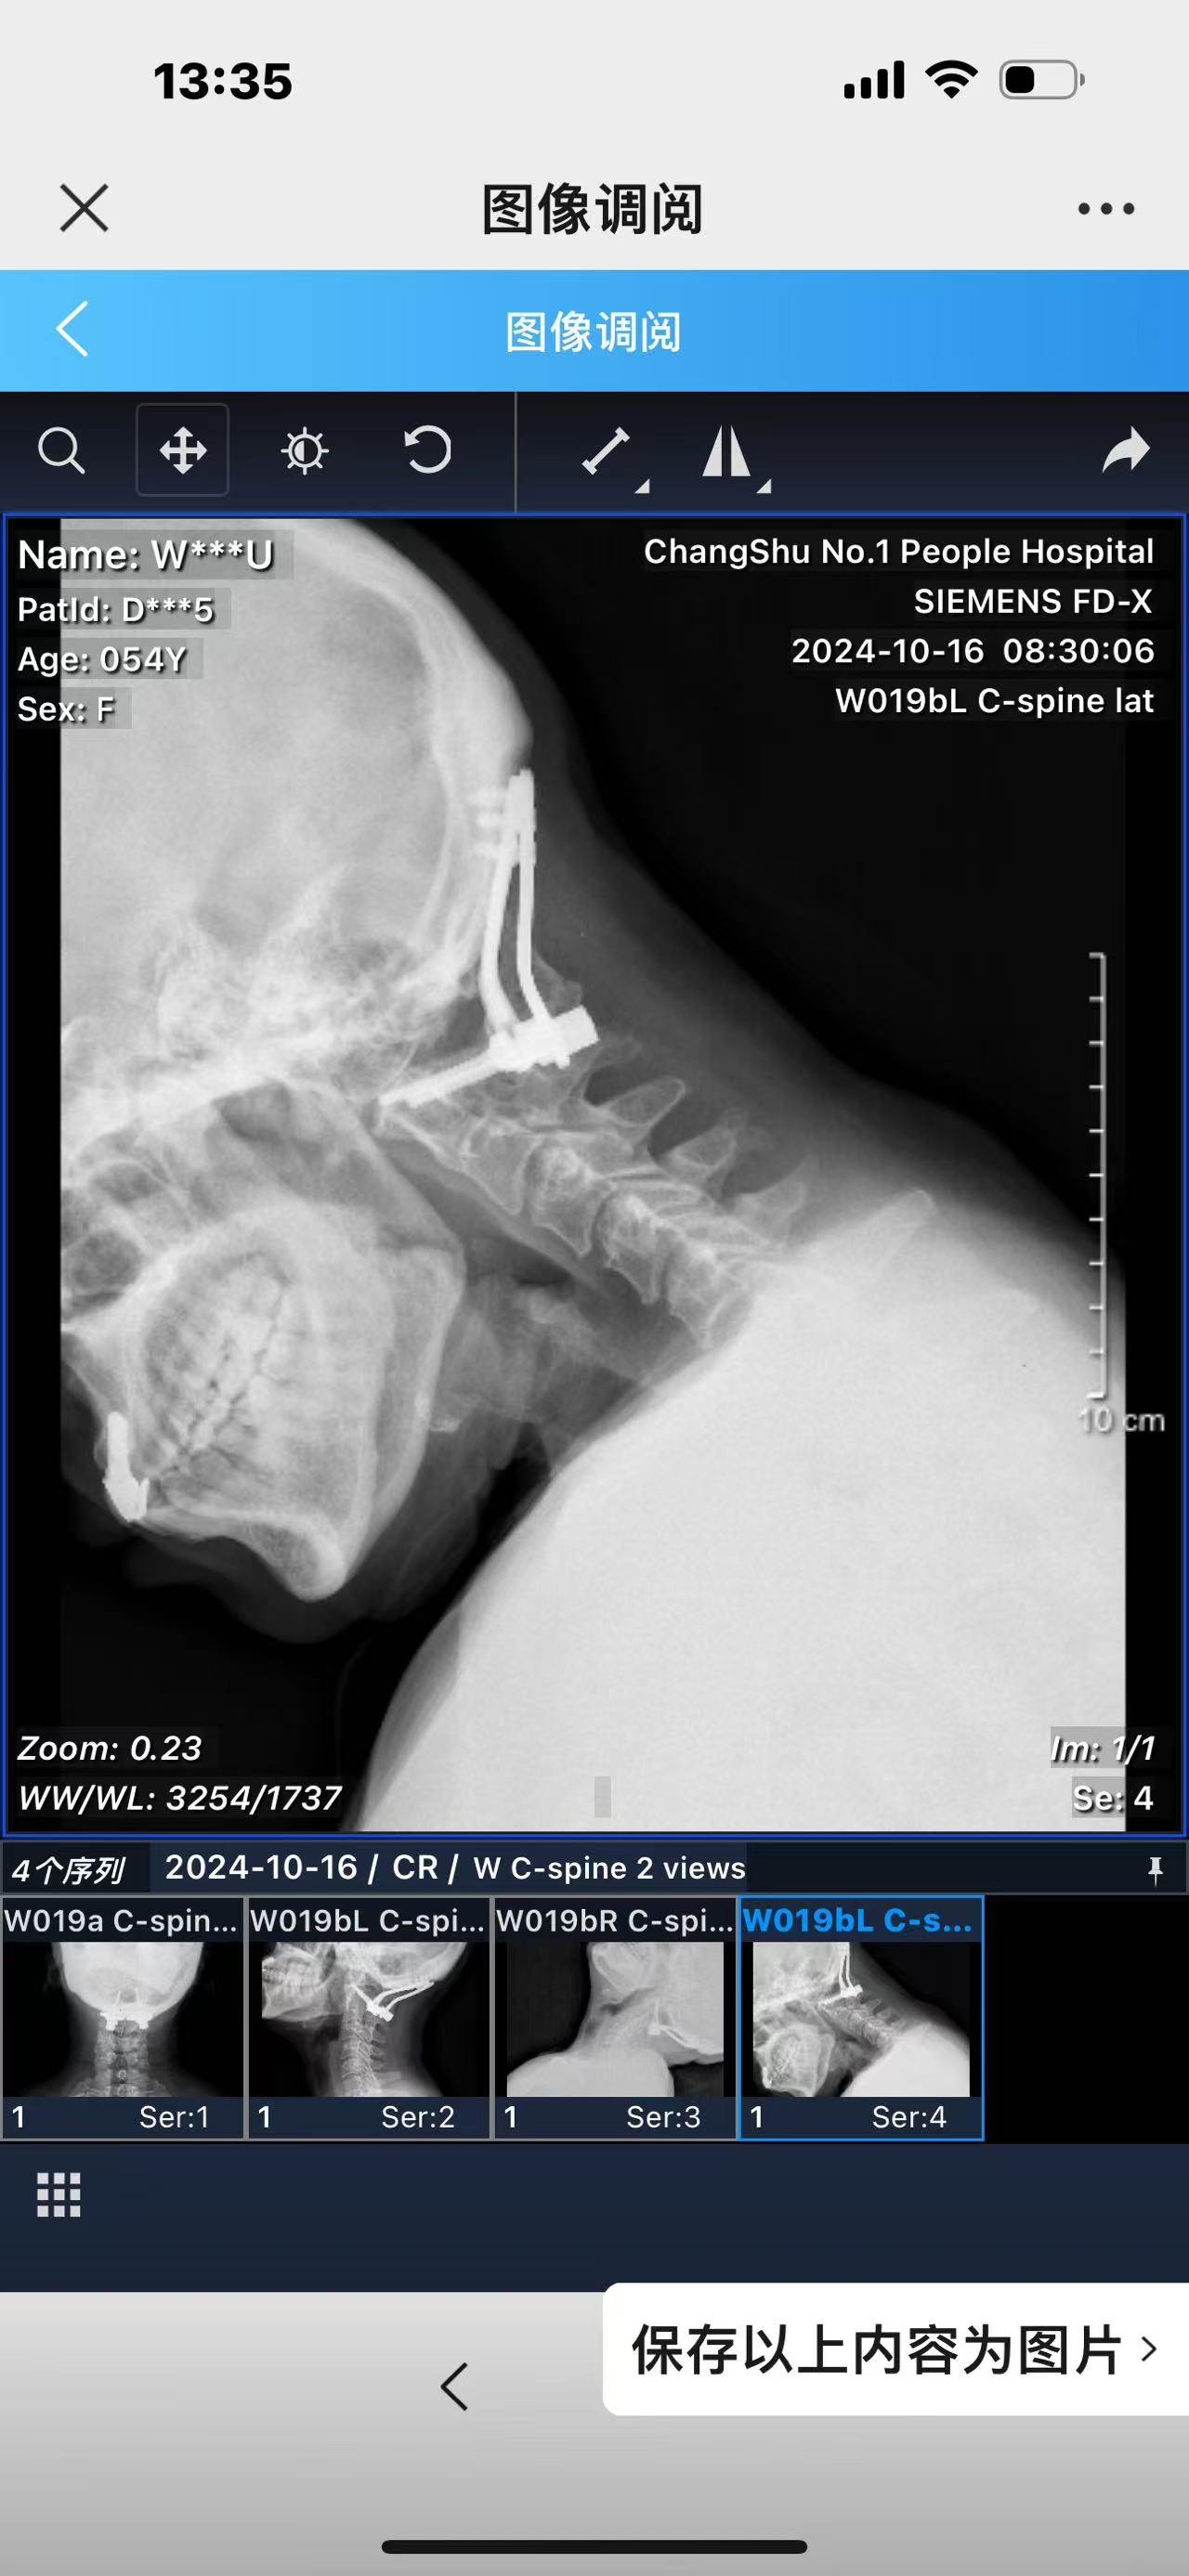

• 2024.10.20,复查,对位良好,偶尔会肩甲骨酸,坐下就不酸。